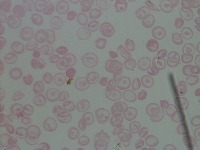

Medical Diagnosis and Research: The "New-Chula" model could be used in medical laboratories and hospitals to automatically identify and classify different cell types in blood samples. This could assist in diagnosing various blood disorders or diseases such as anemia or leukemia, thereby speeding up analysis and treatment processes.

Education and Training: The model could serve as an educational tool for medical students or professionals in training. By using this model, they could learn to identify various types of cells more quickly and accurately, enhancing their understanding of hematology.

Pharmaceutical Trials: During drug testing and development, pharmaceutical companies may use this model to analyze the impact of drugs on different cell types in order to assess effectiveness or side effects.

Public Health Monitoring: Governments and public health organizations could use it to monitor the health condition of the general population, potentially detecting the early stages of an outbreak or epidemic.

Biotechnology Industry: Biotech firms or research labs may use this model for particular research projects involving genetic modification or cellular biology studies where identification and classification of different cell types is necessary.